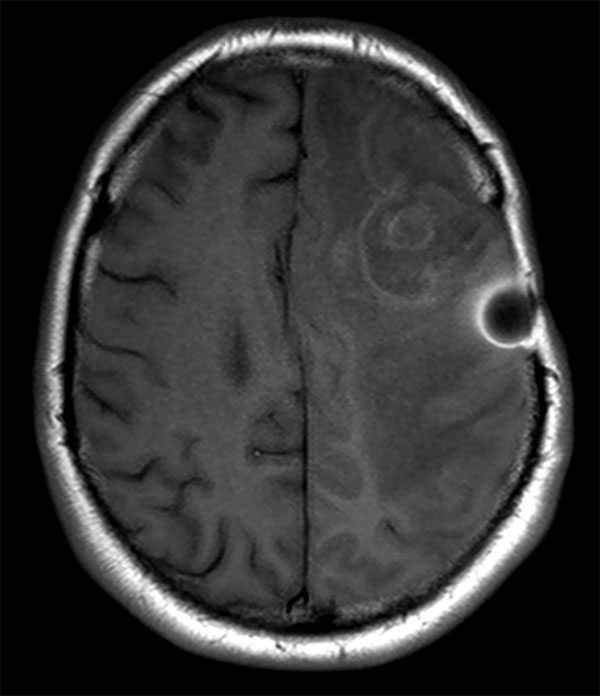

Axial T1w SE (post gado)